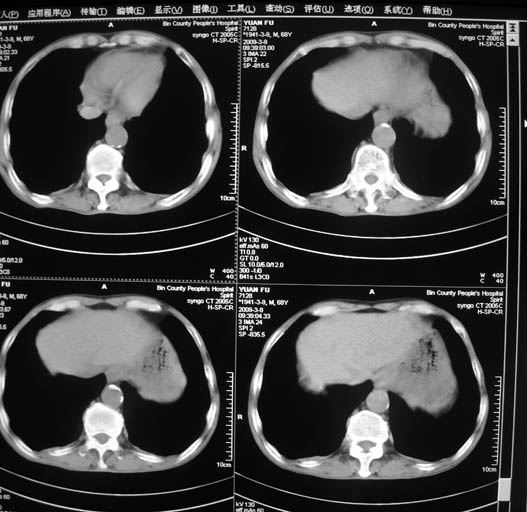

标题: CT18577:男,68岁,左肺占位。

男,68岁,左上肺占位,肺门淋巴结转移?

1)考虑左肺上叶尖段周围型肺癌并阻塞性肺炎,纵隔淋巴结转移。2)心包少量积液。

1)考虑左肺上叶尖段周围型肺癌并阻塞性肺炎,纵隔淋巴结转移。2)心包少量积液

1)考虑左肺上叶尖段周围型肺癌并阻塞性肺炎,纵隔淋巴结转移。

2)心包少量积液。